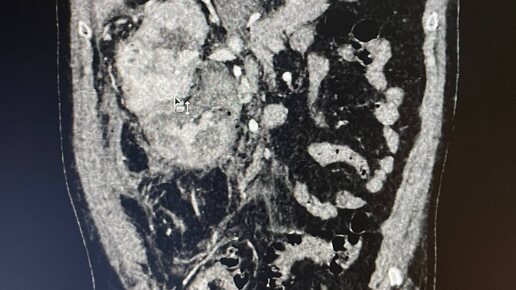

частого в онкологическом стационаре, но редкого в больнице скорой медицинской помощи. К нам на отделение зашли урологи, личное присутствие которых всегда намекает на нечто серьёзное, и попросили в заключении уже описанного исследования добавить классификацию Mayo, так как от этого принципиально зависит тактика лечения пациента с образованием почки. Уверенно сделав вид, что мы поняли о чём речь и сейчас всё допишем, обратились за помощью в интернет, в результате чего классификация была изучена и образованию в почке присвоен уровень II...